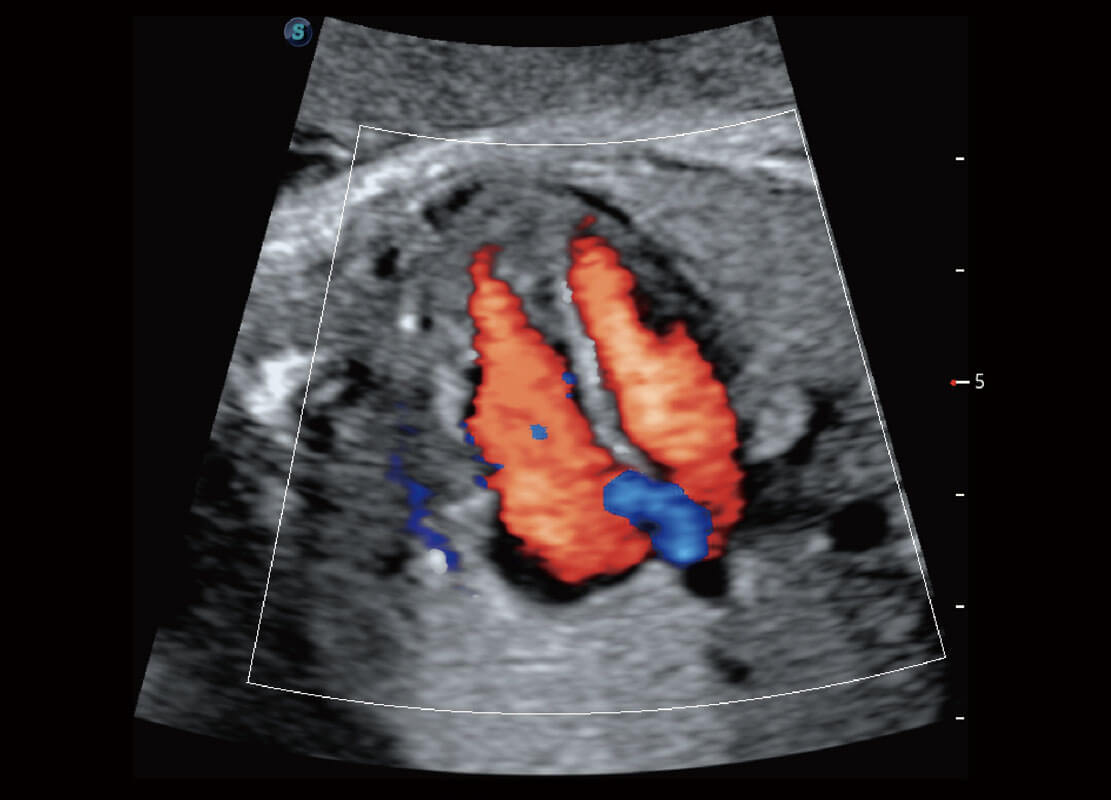

生殖健康

P60优异的图像质量搭载专科探头,在妇科基础疾病的诊断、卵泡生长的监测、输卵管通畅情况的判别等方面为您提供生殖应用方案。

• 胎儿体循环